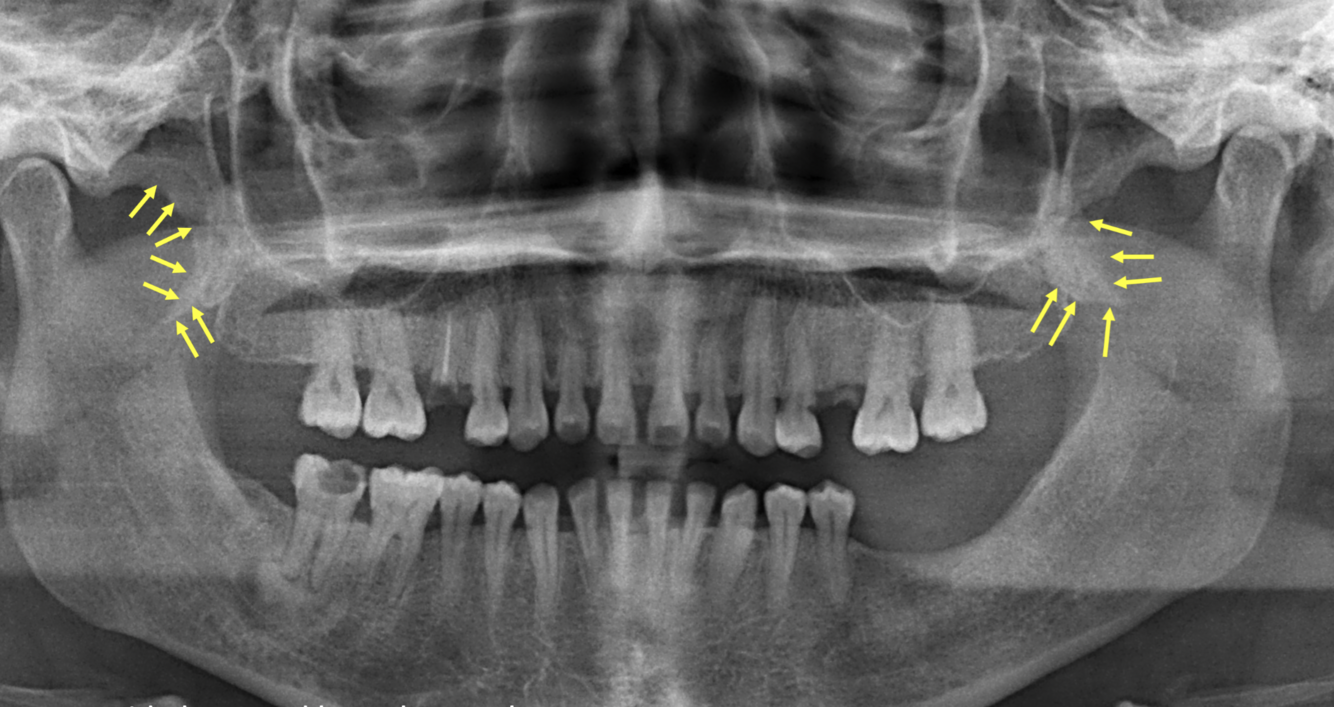

What do the yellow arrows indicate in the following image?

Ears